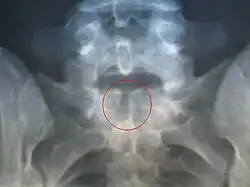

Przepuklina oponowa w 80% przypadków umiejscowiona jest w odcinku lędźwiowym lub krzyżowym kręgosłupa. W 90% przypadków towarzyszy jej wodogłowie.

- zwichnięcie stawu biodrowego obustronne